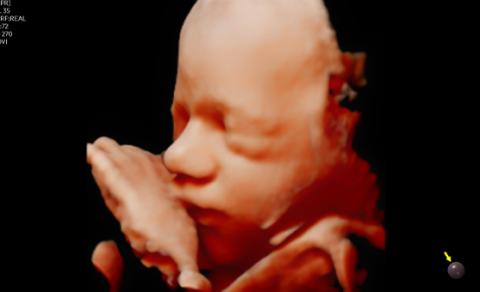

CrystalLive™ in 3D/4D provides users with more realistic and high-resolution images. It outdoes conventional 3D imaging technologies in terms of viewing small parts and lighting effects. In addition, you are able to see 3D anatomy with more realistic depth perception, and can visualize the internal and external structures at once.

CrystalVue™ is an advanced volume rendering technology that enhances visualization of both internal and external structures in a single rendered image using a combination of intensity, gradient and position.

RealisticVue™ ¹ displays high resolution 3D anatomy with exceptional detail and realistic depth perception. User selectable light source direction creates intricately graduated shadows for better defined anatomical structures.